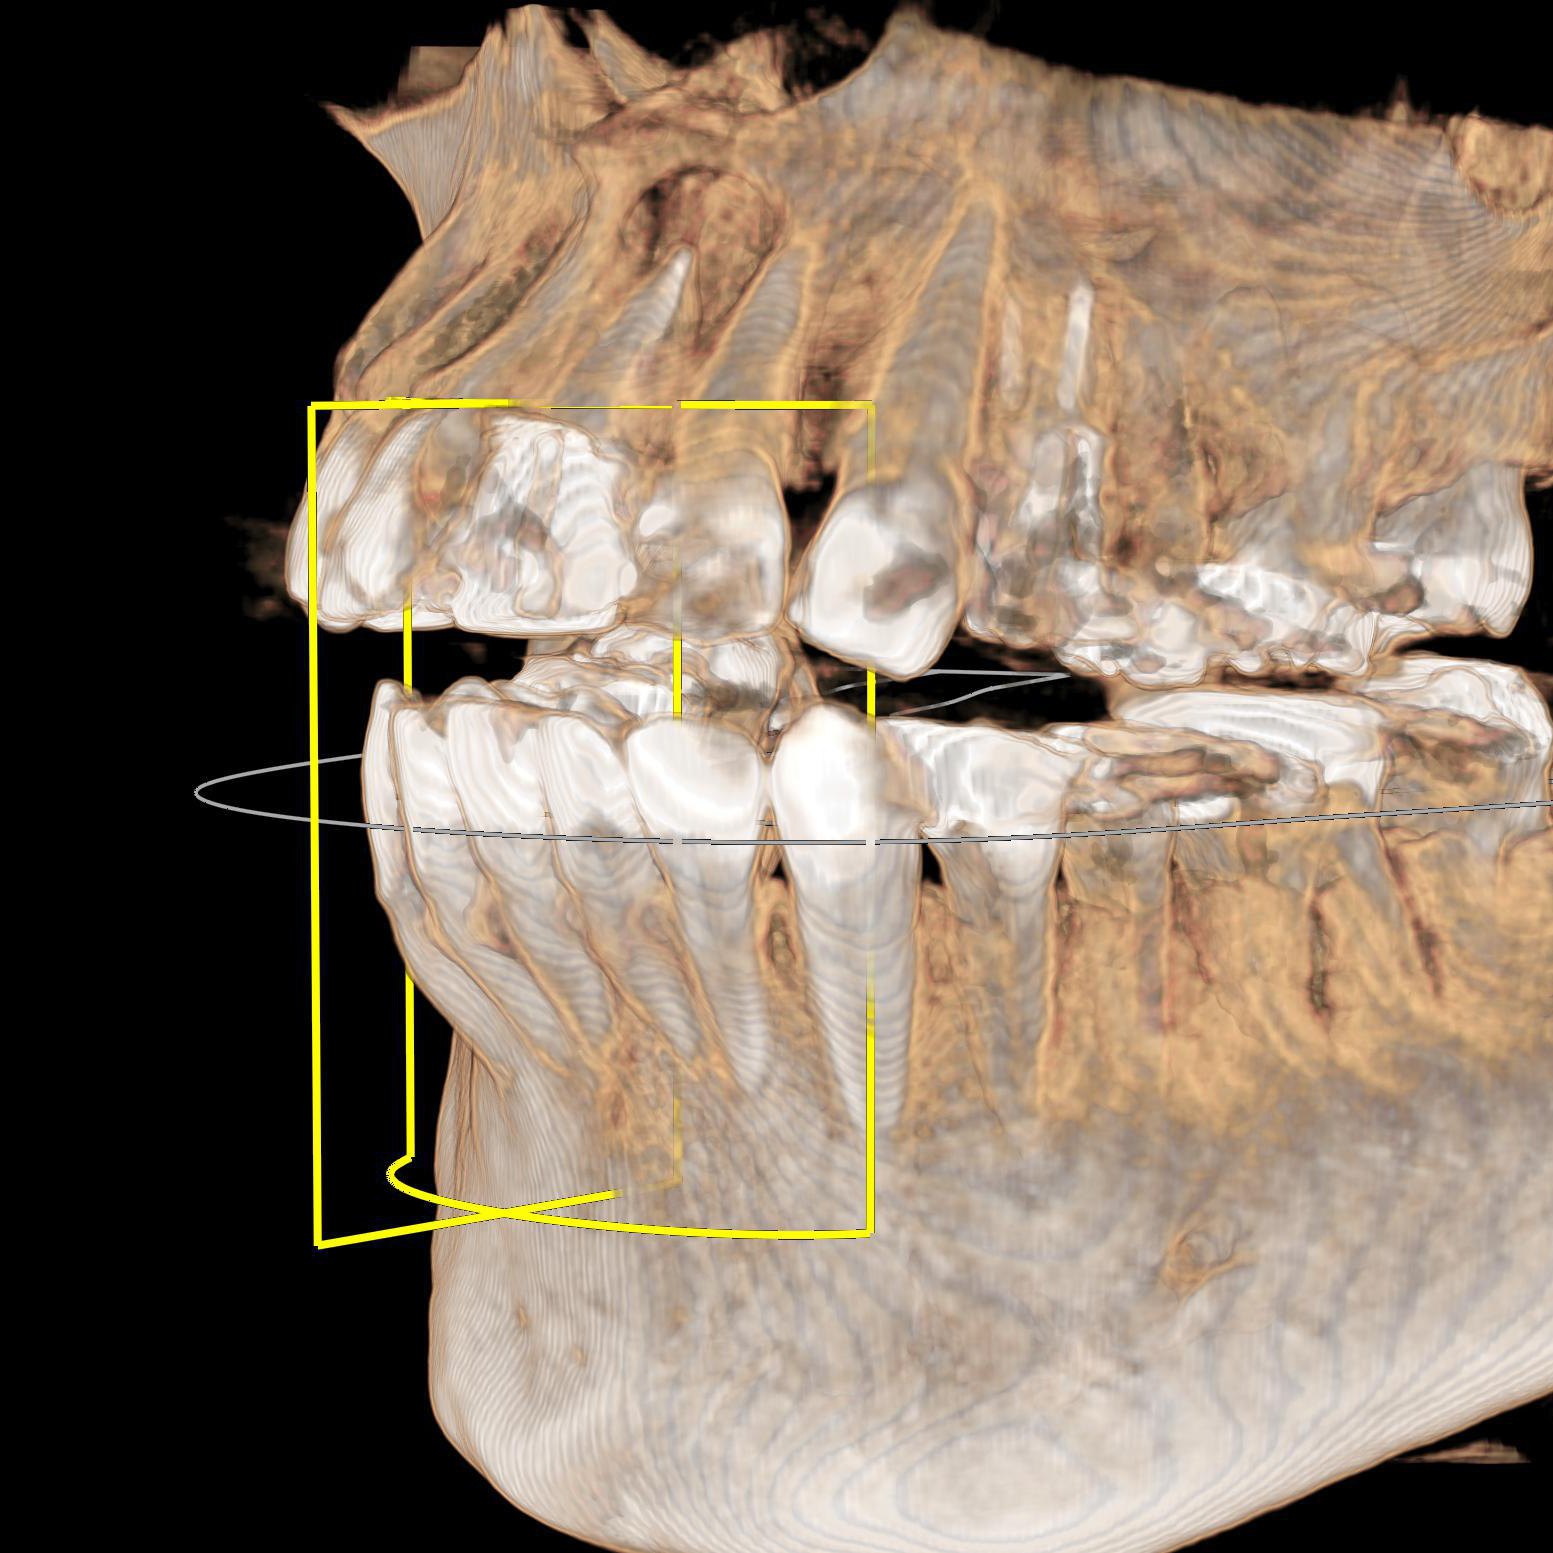

CT(3次元レントゲン)

当クリニックのレントゲンはCTと呼ばれる3次元レントゲン写真が撮影できます。インプラント治療では診査診断には欠かせません。また、親知らずの抜歯や、複雑な根の治療などでも、CT画像が有用な場合が多く、安心、安全はもちろん、精密な治療を行う上でも欠かすことのない診断器械です。